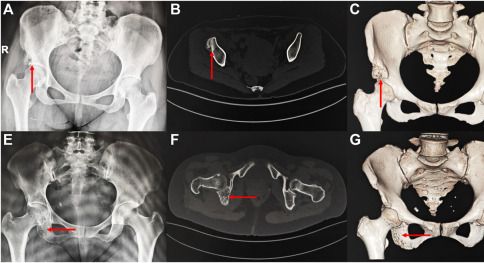

3D打印技术的核心优势在于其能够实现高度个性化的定制。这意味着每一个通过3D打印

技术制作的骨科植入物,都是独一无二的,完全符合患者的解剖结构。